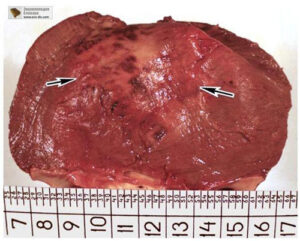

Voglio mostrarvi alcune immagini, in modo che possiate vedere da voi cosa succede al tratto urogenitale e agli altri organi di un uomo che non fa sesso.

Ecco come appare l’infiammazione prostata causata dal ristagno di spermatozoi (quando i testicoli non vengono svuotati). L’infiammazione persistente porta dapprima all’adenoma prostatico, e successivamente al tumore alla prostata (in base alle statistiche, il 38% degli uomini muore per questo motivo). In mancanza di sesso, questo succede sempre ed è per questo che l’adenoma prostatico viene chiamato “la malattia degli anziani”.